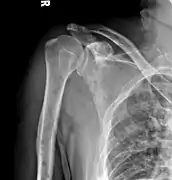

Humerus with multiple myeloma lesions

Same humerus before, with just subtle lesions

The diagnostic examination of a person with suspected multiple myeloma typically includes a skeletal survey. This is a series of X-rays of the skull, axial skeleton, and proximal long bones. Myeloma activity sometimes appears as "lytic lesions" (with local disappearance of normal bone due to resorption) or as "punched-out lesions" on the skull X-ray ("raindrop skull"). Lesions may also be sclerotic, which is seen as radiodense.[70] Overall, the radiodensity of myeloma is between −30 and 120 Hounsfield units (HU).[71] Magnetic resonance imaging is more sensitive than simple X-rays in the detection of lytic lesions, and may supersede a skeletal survey, especially when vertebral disease is suspected. Occasionally, a CT scan is performed to measure the size of soft-tissue plasmacytomas. Nuclear Medicine Bone scans are typically not of any additional value in the workup of people with myeloma (no new bone formation; lytic lesions not well visualized on nuclear bone scan).